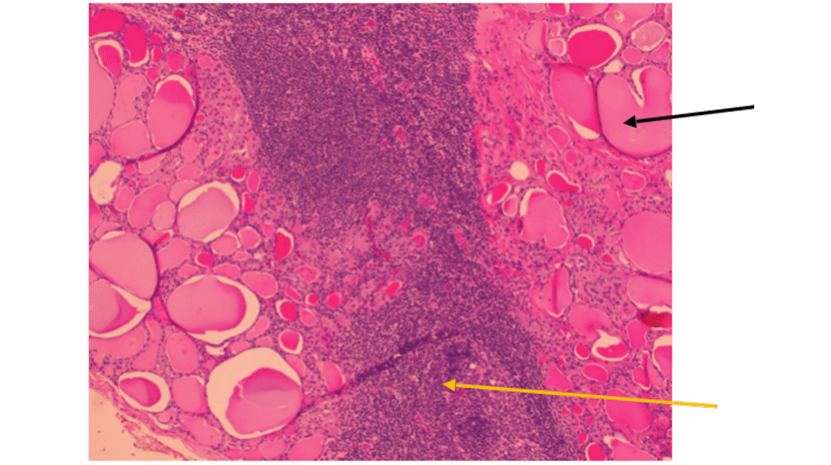

下圖就是顯微鏡下的組織損傷

黑線指的是甲狀腺組織;黃線指的是激戰過後死掉的白血球們